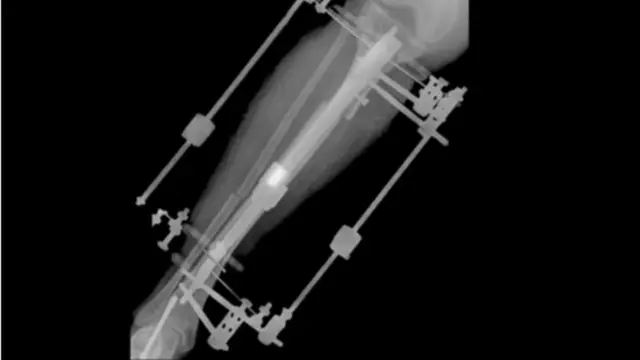

Depoisbullsbet hackerfraturar o osso da tíbiabullsbet hackerEstebanbullsbet hackerdois lugares, os médicos russos colocaram dois dispositivos fixadores externos unidos ao osso com grandes parafusos.

O crescimento do colombiano ocorria lentamente, milímetro a milímetro, dia após dia.

E, depoisbullsbet hackercinco meses, Esteban tinha crescido 5,5 centímetros.

Esteban ficou com os dispositivos presos às suas pernas durante meses e, no começo, tomou calmantes para enfrentar a dor. Ele também teve depressão e perdeu 15 quilos.